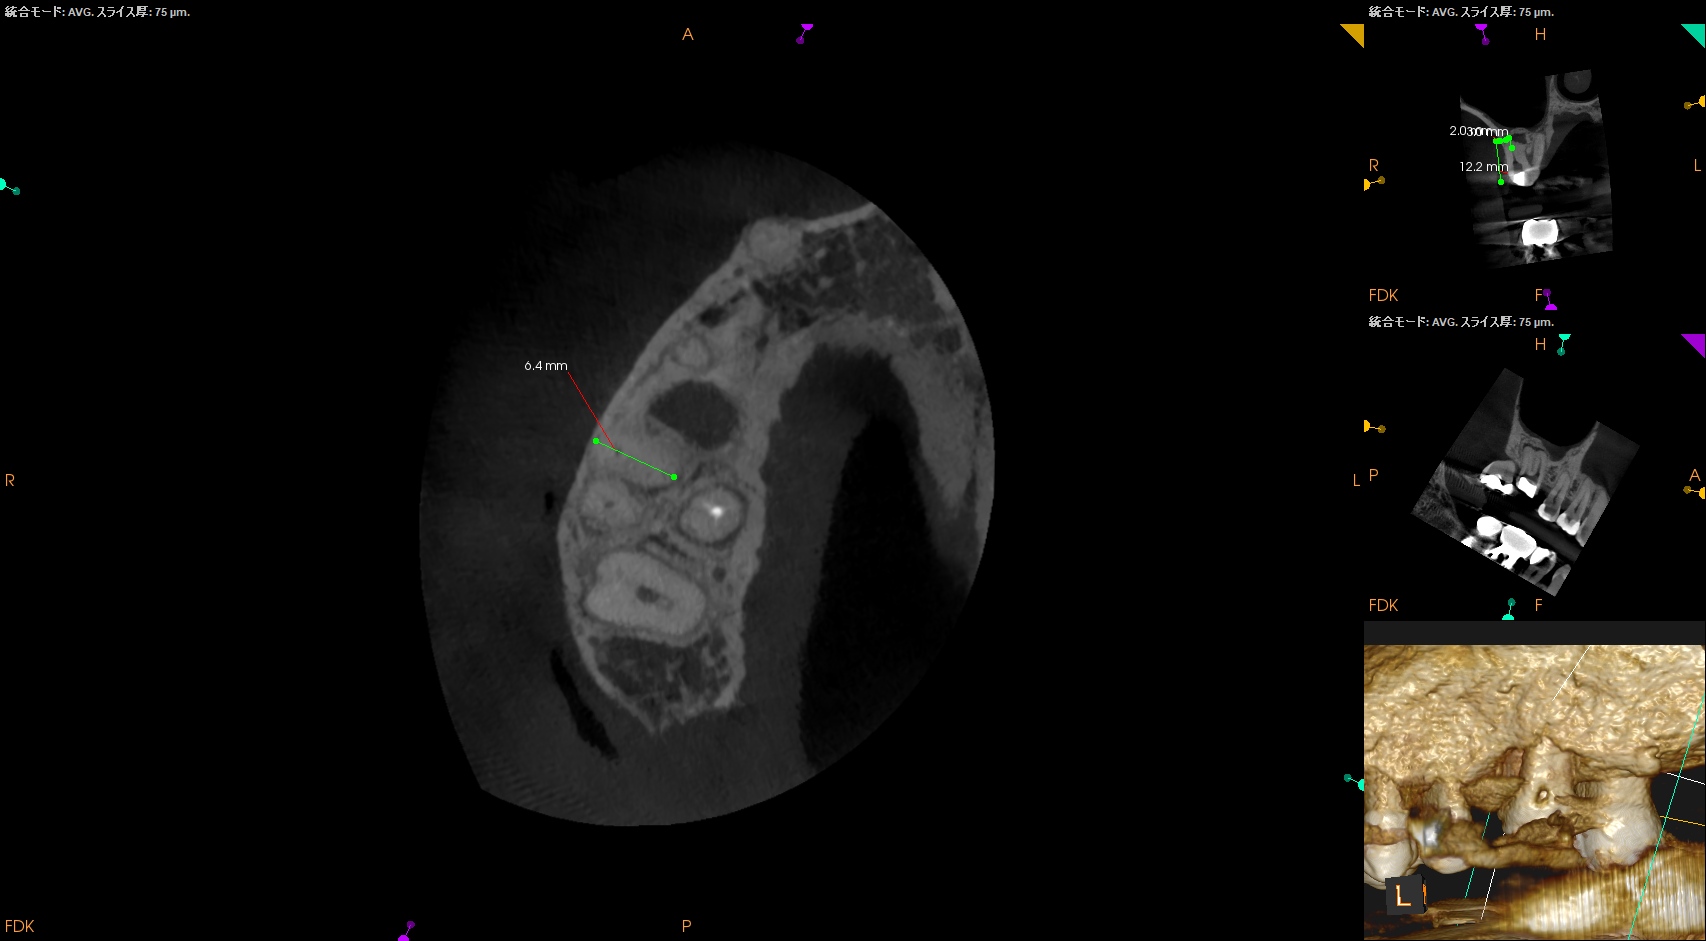

MB,DBのApicoectomyは

MB

CEJよりも12mm下方にMBのApexがあり、

そこを3mm切断するには6.4mmの切断幅が必要である。

そしてMB1-MB2を往復でPrepする必要があり、やや煩雑だ。

中程度の難易度だろう。